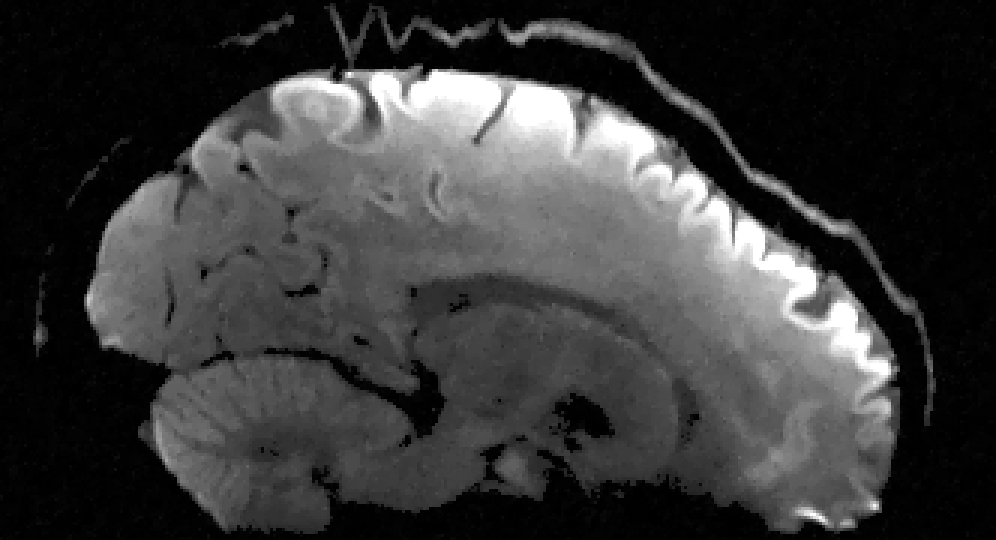

In the second set of evaluations, we considered regularization-based denoising of a 230180 single-channel T1-weighted MR image, obtained by applying complex coil-combination to an 8-channel dataset and subsequently adding simulated complex Gaussian noise. The ground truth and noisy images are shown in Fig. 3.

For reconstruction, the matrix was an identity matrix. Following Refs. [24, 10, 25, 28], the magnitude was regularized using a Huber-function penalty as given by Eq. (28), where a finite difference transformation was used to enforce spatial smoothness of the image. Following Ref. [10, 2, 4, 5, 7], the phase was regularized using a Tikhonov penalty as given by Eq. (29), also using a finite difference transformation to enforce spatial smoothness. All algorithms were initialized with the noisy image.